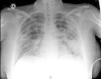

The obstetric examination was normal. A COVID-19 PCR was performed, which was positive. On the blood test, of note were leukocytes 20,900 (98% PMN), lymphopenia with lymphocytes 200, d-dimer 578ng/ml, CRP 28mg/dl, LDH 223U/l, and procalcitonin 5.33ng/ml. From a respiratory point of view, with oxygen via nasal cannula at 3L, she had a PO2 of 140mmHg. On the chest X-ray, multilobar bilateral pulmonary infiltrates with an interstitial-alveolar pattern were observed, with alveolar consolidation in the left upper lobe, blunting of the costophrenic angles, and right fissural thickening due to a small amount of pleural effusion (Fig. 1).